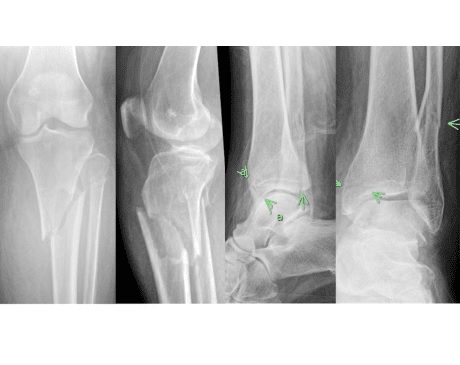

I was hit by car, had a compound fracture with a bone sticking out of my left foot. Broken tibia and fibia?. Screwed plate and bones back together. I am healing fine, next visit 3/26 to remove stiches. I seem to have total function of foot. Still have 2 more weeks of not using leg, but very hopeful.